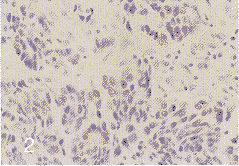

p16蛋白表达在84例食管癌中阳性46例,阳性率为54.8%。p16蛋白主要位于细胞浆,部分位于细胞核,呈棕色、均匀的细胞颗粒着色(见插页第4页图2),阳性细胞以局灶分布为主,部分呈散在分布,其它细胞和间质无阳性反应,正常食管粘膜部分阳性细胞位于粘膜上皮基层,散在分布。84例食管癌中37例Rb表达阳性,阳性率为44.0%;Rb蛋白定位于细胞核,呈棕黄色、细颗粒着色,阳性细胞分布在同一标本上表现为多样性。(见插页第4页图3)。正常粘膜未见阳性反应。

图2 食管鳞癌组织 p16蛋白定位于细胞核,呈棕黄色细颗粒状。S-P法×150

图3 食管鳞癌组组 Rb蛋白定位于细胞浆及细胞核中,呈颗粒状不均匀棕黄色。S-P法×150